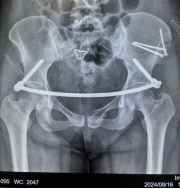

8月15日,颍上县人民医院骨科依托蚌埠医科大学第一附属医院紧密型医联体建设工作,通过专科针对化帮扶,由蚌埠医科大学主任医师吴敏教授开展手术带教与示范指导,成功开展骨盆骨折切开复位螺钉联合infix钉棒系统内固定术。

34岁的李梅(化名)因车祸受伤入院,我院将其影像数据及病情实时共享至蚌埠骨科专家团队,并在专家团队指导下完成了手术。

此前我院缺乏开展此类手术的经验,该类患者一般转至上级医院治疗。现在有蚌医骨科背后强大团队做依托,通过“传、帮、带、教”,开启了骨科手术新篇章,拓展了新的技术项目,意味着日后对疑难重症患者救治将得到有力的后援支持。